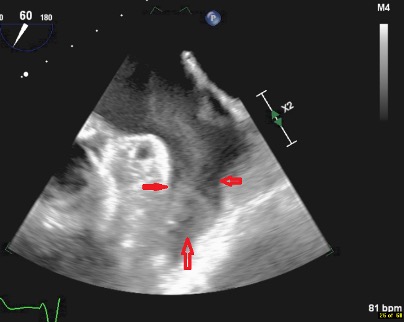

No embolic lesions were visualized on computed tomography (CT) scans of the chest, abdomen, and pelvis. TEE findings were negative for any lesions on the pacemaker leads or valves (Figure 1). However, given the lack of an alternative explanation for his persistent bacteremia, it was decided to extract the pacemaker. Intraoperative TEE revealed a patent foramen ovale (PFO) (Figure 2) and a thrombus in the left atrial appendage (Figure 3) but revealed no masses on the pacemaker leads or cardiac valves. However, during the extraction procedure, the superior vena cava leads were found to be encased in significant amounts of thrombus.

Figure 1. TEE image showing the right atrial lead (downward-pointing arrows) traversing the right ventricle on its way to the right atrium. The right ventricular lead is indicated by the upward-pointing and sideways-pointing arrows. No vegetations were present.